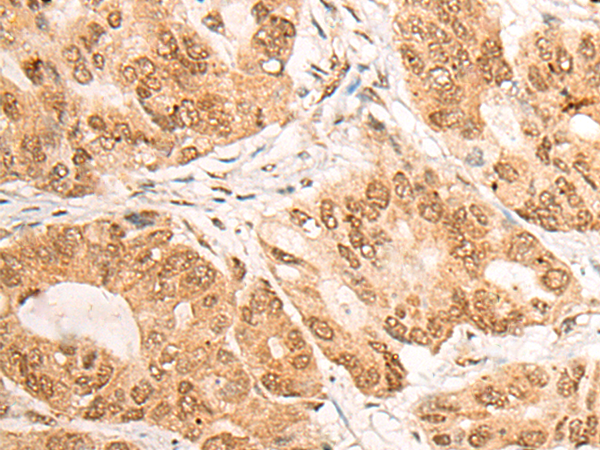

IHC positive control:

Human colorectal cancer;

IHC Recommend dilution:

20-100